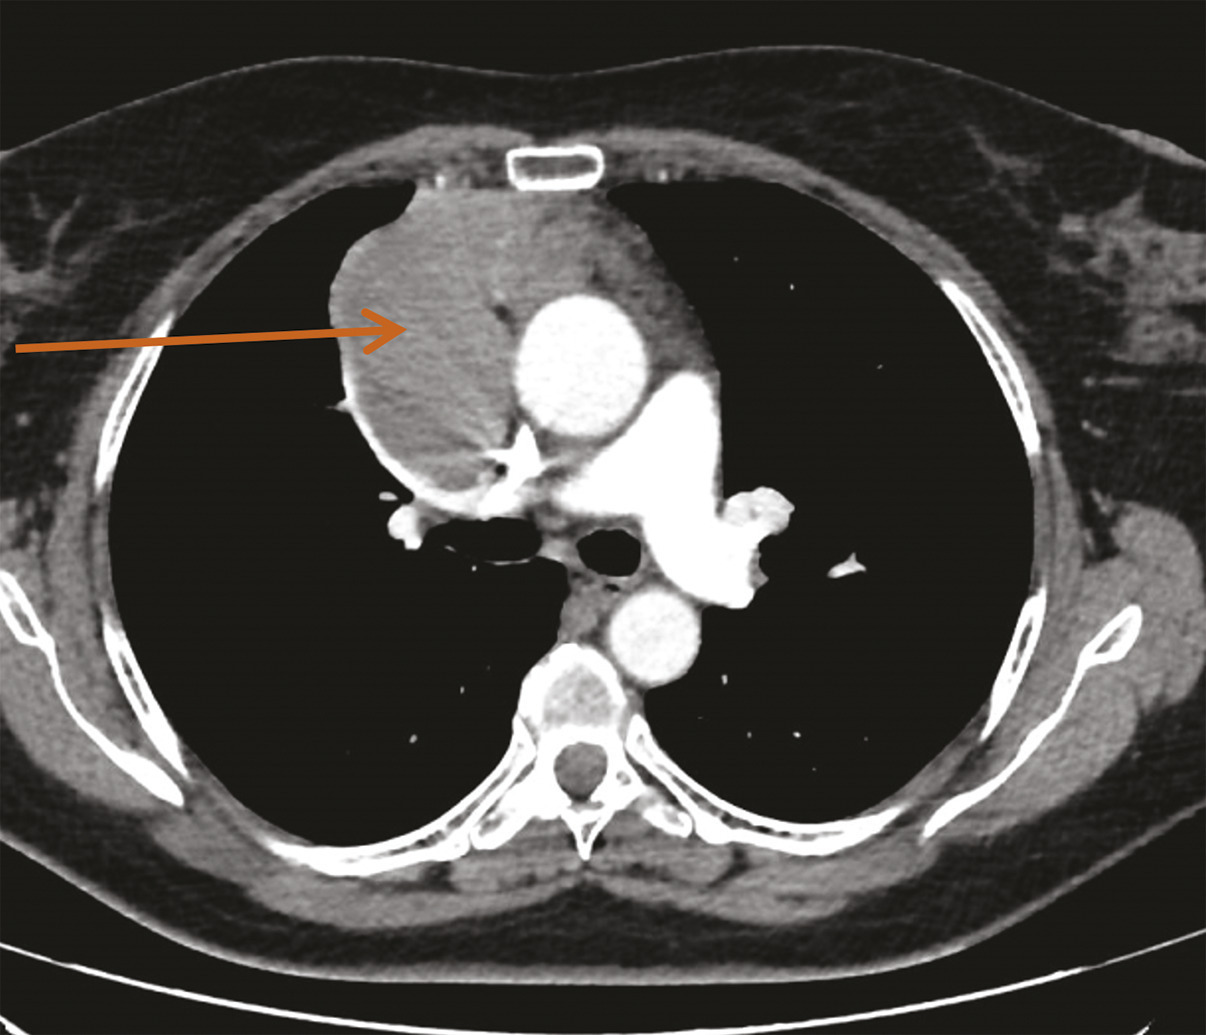

Une imagerie par résonance magnétique (IRM) du crâne réalisée 15 jours après le début des symptômes n’a pas montré d’anomalie. Toutefois, leur persistance et leur aggravation ont fait demander à son médecin traitant un dosage des anticorps antirécepteurs à l’acétylcholine, qui s’est révélé positif, conduisant au diagnostic de myasthénie. Des anticholinestérasiques ont alors été prescrits en première intention, permettant d’améliorer transitoirement les symptômes musculaires. Leur effet est de prolonger l’action de l’acétylcholine au niveau de la membrane post-synaptique par blocage réversible de l’acétylcholinestérase (deux médicaments sont disponibles : la pyridostigmine et l’ambénomium). Dans le cadre du bilan de cette myasthénie, une tomodensitométrie thoracique est pratiquée, qui met en évidence une masse médiastinale antérieure, volumineuse et polylobée évoquant une tumeur thymique (fig. 1).1

Le dossier de Mme C. est discuté en réunion de concertation pluridisciplinaire (RCP) RYTHMIC (Réseau tumeurs thymiques et cancer ; www.rythmic.org). Face à cette volumineuse masse thymique avec un doute sur sa réséca­bilité d’emblée, il est décidé dans un premier temps de s’assurer du diagnostic par une biopsie, qui est réalisée par ponction transthoracique. L’analyse du prélèvement effectué confirme le diagnostic de thymome de sous-type B2.

Une évaluation neurologique est nécessaire afin d’encadrer le geste chirurgical. Mme C. reçoit ainsi en préopératoire une injection d’immunoglobulines par voie intraveineuse afin d’éviter une exacerbation des symptômes myasthéniques en périopératoire. La chirurgie consiste en une sternotomie médiane, avec exérèse de la tumeur médiastinale et bilobectomie supérieure. Face à l’envahissement péricardique et pulmonaire adjacent, la tumeur est classée stade III (dans la classification de Masaoka-Koga), et stade T3N0M0, soit IIIA (dans la classification TNM). Les marges de résection sont saines (R0).6, 7